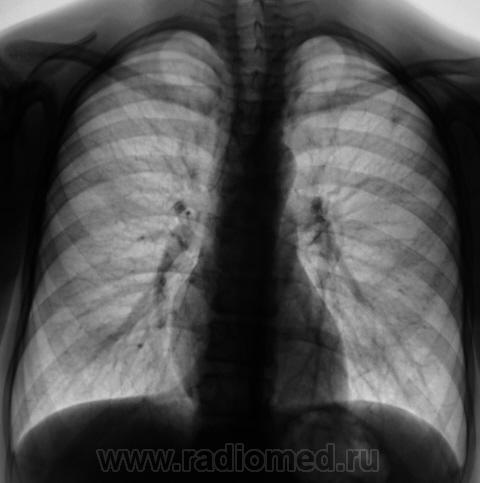

При расшифровке флюорограмм "взят на контроль". Подросток, первичная постановка на военный учёт. Жалоб нет.

Это уже не зона агрессии а конкретная тень.

Первая флюорограмма. Конечно, взяли на контроль. Разрезали. Сейчас выложу томограммы. Томограммы, как и всегда с "букетом роз".

А рентгенологически, что выставлять? Очаговый?

Два сегмента очаговый, больше двух диссеминир.

м.б.реальная картинка выглядит по -другому,но в туб. дисп. б-го направлять не с чем. я бы сделала лордоз и получила бы срез сосуда(сосуд.мальформация),тк достоверных очагов на тмг не получ.м.б назнач. бы контроль ч\з 3 мес. причины "играть" в кт не было.

Возможно, Вы правы. Но мы выставили очаговый. Записали изображение на диск в цифровом формате, фтизиатры забрали себе.

Конечно, ответственность, подросток и все такое... Но с другой стороны, кроме мелкого кальцинатика прицепиться больше не к чему. Все очаговоподобные тени видны при уменьшенной яркости и в местах пересечения сосуда с кортикалом ребра. Либо имеют "хвостик", что указывает на сосуд. Такое мое мнение.